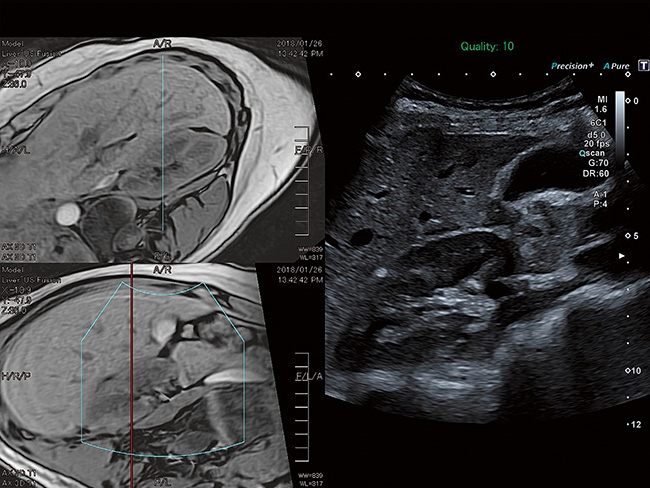

Aplio a550 может работать с линейным матричным датчиком и поддерживает новейшие монокристаллические датчики. Также Aplio a550 поддерживает большое количество дополнительных опций, таких как - SMI, Компрессионная эластография, Эластография сдвижной волны, Smart Fusion, исследования с использованием контраста (CEUS), 3D реконструкции в реальном времени (4D), функции автоматической оценки подвижности миокарда и фракции выброса.

IFusion:

Да